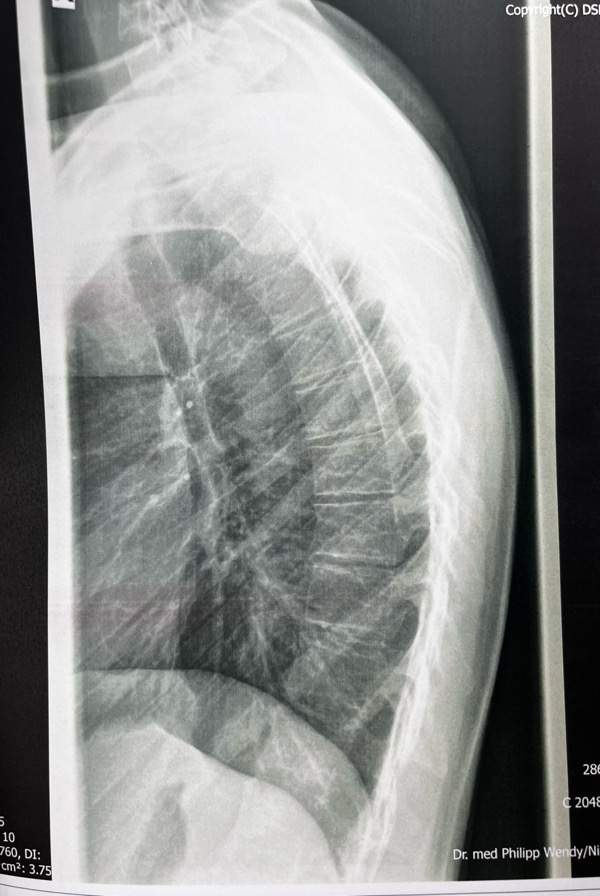

Ich dachte ich stelle hier nun mal die Bilder ein. Einmal von der Seite und von vorne. Der Bericht mit der Diagnose ist auch dabei. Kann jemand anhand der Röntgenbilder offensichtliche Keilwirbel erkennen und vielleicht auch grob was zu dem Kyphosewinkel sagen. Ich selber glaube Ansätze von keilwirlbel zu sehen, aber ich bin mir nicht sicher.

- A016A6EA-EA2D-4024-AE48-A1A98313B03A.jpeg

- Ansicht von der Seite im stehen

Die Messung vom BWS Kyphosewinkel erfolgt mittels der sogenannten Neutralwinkel, das sind die Wirbel am Wendepunkt zur HWS Lordose und der LWS Lordose. Der HWS Übergang ist schwer zu sehen und der LWS Übergang kaum sichtbar, weil es nur eine BWS Aufnahme ist.

Deshalb sollte immer eine Röntgen-Ganz-Aufnahme (LWS, BWS und HWS) gemacht werden. Frau Dr. von Ricthofen kann solche Aufnahmen machen. Grob kann ich nur sagen, dass die in der Diagnose erwähnte "vermehrte Kyphosierung" bzw. später im Text "leicht vermehrte Kyphosierung" nachzuvollziehen ist.

Es sieht für mich aber so aus, als ob der obere Kyphosebogen zu flach ausgeprägt ist.

Also grundsätzlich finde ich die Beantwortung dieser Fragen problematisch, weil das den Ärzten bzw. den Spezialisten vorbehalten ist und Dich aktuell auch gar nicht weiterbringen würde.Kann jemand anhand der Röntgenbilder offensichtliche Keilwirbel erkennen und vielleicht auch grob was zu dem Kyphosewinkel sagen

Was die Skoliose in der Diagnose angeht, die beginnt per Definition erst ab 10° und ist bei Erwachsenen oft bis ca. 20° nicht relevant.

Ich habe mir deine Bilder angeschaut. Da ich selber zig Bilder analysiert und mit Software ausgemessen hab, kann ich dir folgendes mitteilen:

- Der globale Cobb-Winkel, definiert als der Winkel zwischen dem meist geneigten BWS-Wirbel im unteren Segment (das ist häufig T11 oder T12) und dem meist in-die-andere-Richtung-geneigten BWS-Wirbel im oberen Segment (T1 bis T4 häufig) kommt bei dir auf ca. 55 Grad zu belaufen.

- Manchmal wird auch implizit der Stagnara-Winkel gemessen, und als Cobb-Winkel ausgewiesen. Dieser ist strikte definiert als der Winkel zwischen T4 und T12 und wird häufig angewendet, weil die oberen Wirbel (T1 bis T3) auf dem Bild nicht klar ersichtlich sind. Da ich nicht genau identifizieren kann, welcher Wirbel welcher ist, kann ich es nicht genau sagen, ich schätze aber auch hier, dass 42 Grad zu tief bemessen ist.

- Viele deiner BWS-Wirbel sind milde verkeilt (zwischen 5 und 10 Grad). Man spricht von Keilwirbel ab 5 Grad. Das ist nicht sonderlich viel und wird leider von vielen Docs/Spezialisten komplett übersehen. Wenn mehrere Wirbel betroffen sind, führt das aber sehr schnell zu einer strukturellen Verkrümmung, genau so wie in deinem Fall.

- Die einzige Bedingung, die für eine Diagnose des klassischen Morbus Scheuermann erfüllt sein muss, ist, dass drei oder mehr aufeinander folgende BWS-Wirbel eine Keilform von 5 Grad oder mehr haben. Daneben gibt es eine Reihe von radiologischen Eigenschaften, welche alle auf einen Morbus Scheuermann hinweisen bzw. gehäuft mit diesem in Erscheinung treten, nicht aber notwendig für die Diagnose sind: Schmorl-Knoten, Grund- und Deckplatten-Unregelmässigkeiten, verschmälerte Zwischenwirbelräume, globaler Cobb-Winkel von mehr als 40/50 Grad (je nach Quelle und Messmethode).